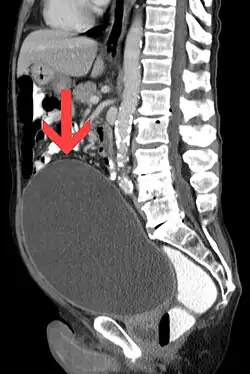

Urinary retention with greatly enlarged bladder as seen by CT scan.

As seen on axial CT